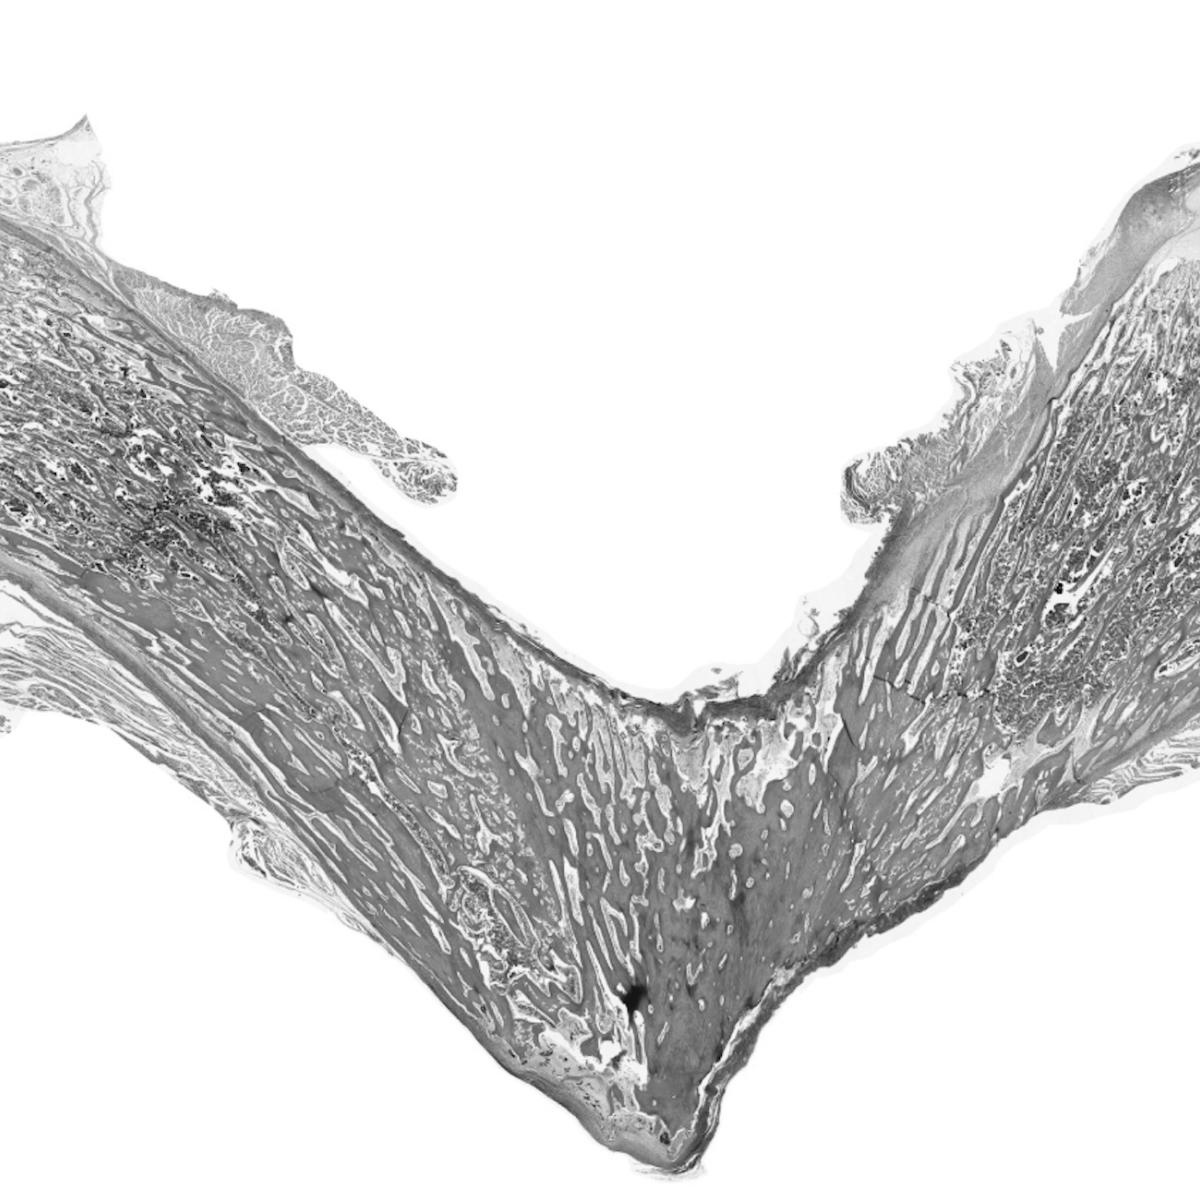

Pyle’s extensive study of the biological underpinnings of Duchenne muscular dystrophy has led to several significant breakthroughs. She developed a first-of-its-kind roadmap of human skeletal muscle formation and devised strategies to generate skeletal muscle cells and somites, the cells that give rise to skeletal muscles, bones and cartilage during development, from human pluripotent stem cells. Each of these discoveries represents a major step toward the development of a cell replacement therapy for Duchenne.